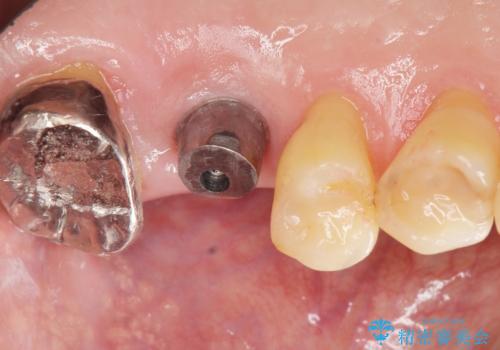

奥歯のインプラント ソケットリフト 60代男性

- 奥歯のインプラントをご希望し、来院された患者様です。

精査したところ上顎骨の厚みが薄かったため、ソケットリフト(上顎洞底挙上術)を併用してインプラント治療を行いました。

インプラントの種類:スプライン ツイスト (保証期間:5年)

クラウンの種類:ベレッツァクラウン (オールセラミック)

固定様式:セメント固定